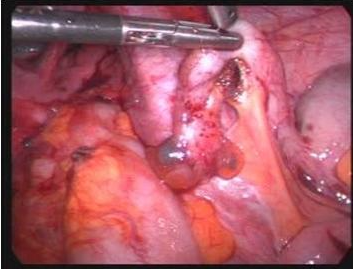

LESÃO DE ENDOMETRIOSE